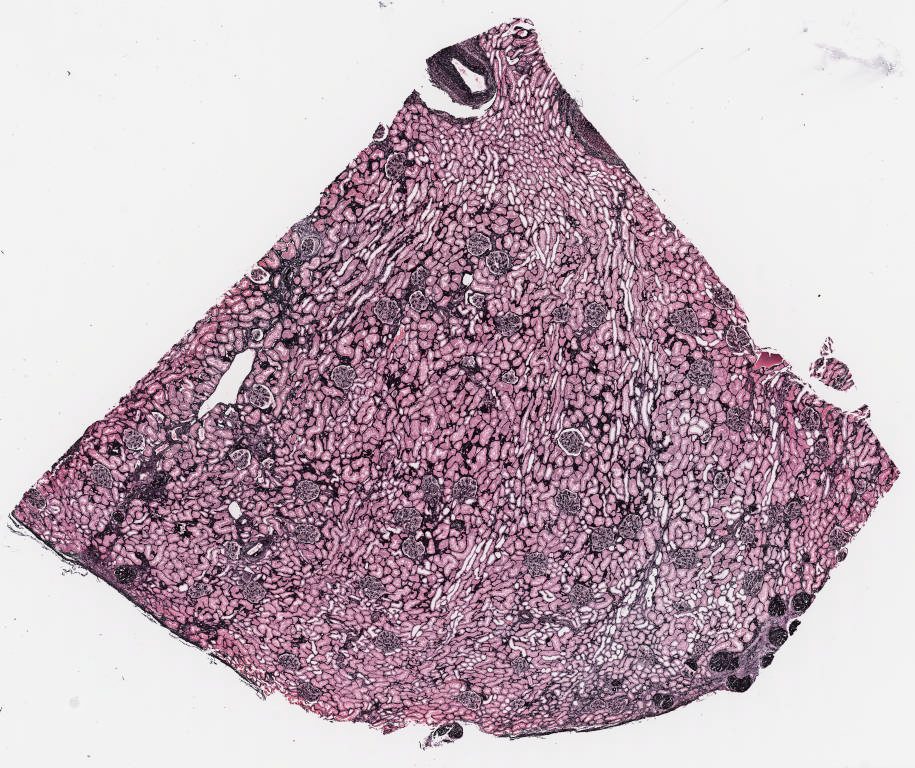

P - Jones.svs

27607 x 23168

@ 40X